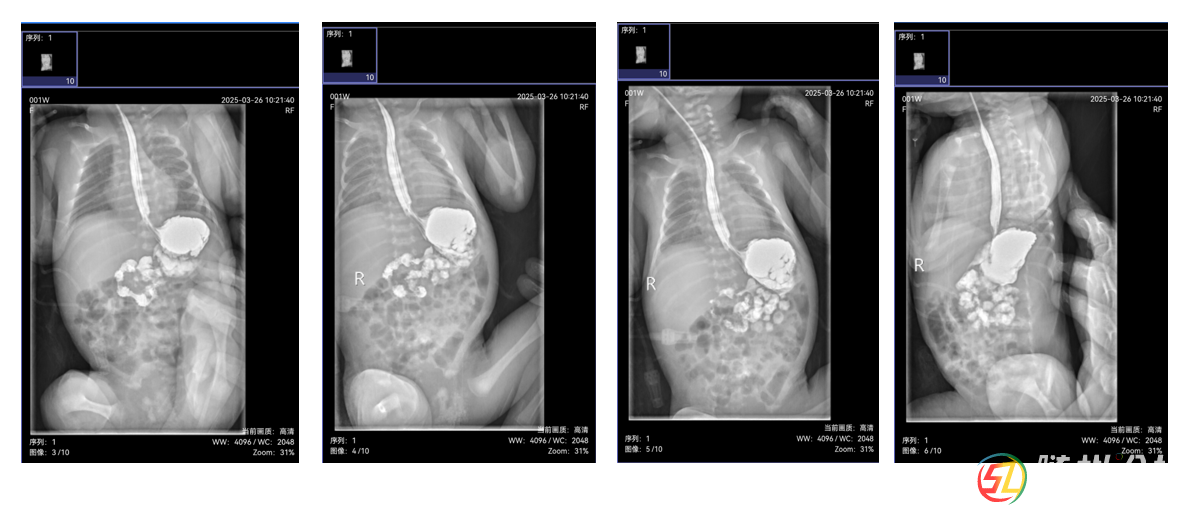

由于新生兒消化道畸形診斷技術(shù)要求高,隨州市中心醫(yī)院新生兒科副主任涂小瓊迅速啟動(dòng)多學(xué)科協(xié)作機(jī)制,聯(lián)合本院超聲影像科副主任醫(yī)師涂朝霞行幽門管超聲檢查、醫(yī)學(xué)影像科副主任楊永剛行上消化道造影檢查,并積極聯(lián)系武漢兒童醫(yī)院新生兒內(nèi)科主任曾凌空教授、放射影像科主任彭雪華教授開展遠(yuǎn)程會診。

會診中,彭雪華教授詳細(xì)解讀影像資料,明確診斷為“可復(fù)性胃翻轉(zhuǎn)”,排除了幽門肥厚;曾凌空教授結(jié)合患兒情況,制定了科學(xué)的喂養(yǎng)方案和后續(xù)治療計(jì)劃。此次會診不僅為朵朵的康復(fù)指明了方向,也為隨州市中心醫(yī)院積累了新生兒消化道畸形診斷的寶貴經(jīng)驗(yàn)。